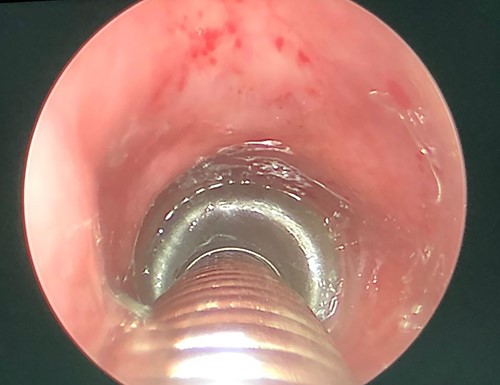

Flexible laryngoscopic examination of the larynx, showing left sided polypoidal mass.

A thorough otorhinolaryngology examination was done and revealed clear oral cavity as well as normal dental health condition. On flexible laryngoscopic examination, a 2 × 1-cm yellowish polypoidal mass covering left vocal cord was found with mild signs of reflux (Fig. 1).